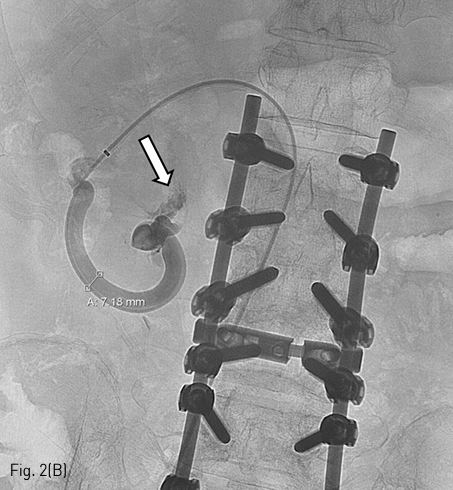

초음파 유도하에 우측 총 대퇴정맥을 천자하여 6 French Balkin sheath insertion 후 우측 신장정맥으로 유입되는 장간막신장정맥 단락내의 입구까지 진입시켰다 (Fig. 2A). 정맥류가 성선정맥으로 측방으로 연결되어 연결점을 찾기 어려웠으나 5 French catheter (Cobra: Angiodynamics, Queensbury, NY, USA)와 0.035-inch hydrophilic guidewire (Radiofocus; Terumo, Tokyo, Japan)로 선택에 성공하여 portal vein 방향으로 진입을 시도하였다. 과도한 굴곡으로 진행이 어려워 microwire (Meister: Asahi Intecc, Nagoya, Japan) 와 2.2 French microcatheter (Progreat: Terumo)를 사용하여 혈류 방향에 역행 (retrograde approach) 하여 십이지장 제 2부에 있는 정맥류까지 진입하고 정맥 조영술을 시행하였다. 십이지장으로 활동성 출혈 (Fig. 2B)이 관찰되어 microcatheter를 조금 더 혈류 방향에 역행하게 진행하여 유출 정맥을 detachable microcoil (Concerto: Medtronic, Sunnyvale, CA, USA) 5개로 색전술을 시행하였다. 확실한 차단을 위해 문맥에서 원위부를 8 mm Amplatzer vascular plug type IV (St Jude Medical Inc., Saint Paul, MN, USA)로 막은 후 microcoil과 vascular plug 사이로 microcatheter를 위치한 후 Gelfoam 1000 micrometer (Caligel: Alicon, Hangzhou, China)으로 추가적인 색전술을 시행하였다 (Fig. 2C). 이후 vascular plug를 detach 하고 시술을 종료함.

Fig 2C

(C) After embolization of proximal (microcoils) and distal (plug, arrow) portion of the bleeding focus, fluoroscopic image shows stasis of variceal flow by Gelfoam injection via microcatheter.